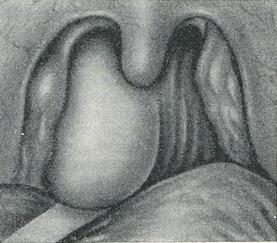

Симптоми. Абсцес протікає при підвищеній температурі (до 39-40°). Поперхіваніе і болю при ковтанні ведуть до відмови від їжі; нерідко їжа потрапляє в ніс і горло. Спостерігається також утруднене носове дихання, голос стає глухим, невиразним, дихання супроводжується хрипінням, що посилюється під час сну. При огляді носоглотки визначається припухлість, що локалізується частіше трохи вище м'якого неба, ближче до одній половині глотки (рис.).